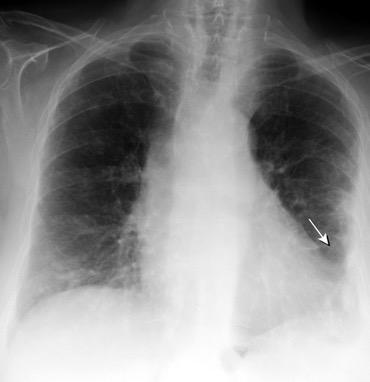

Visible en radiografías en decúbito supino de los pacientes con neumotórax por la acumulación de aire en el seno costofrénico.

“Deep sulcus sign”. Seno costofrénico aumentado en anchura y profundidad

Polireddy K et al. Blunt thoracic trauma: role of chest radiography and comparison with CT findings and literature review . Emerg Radiol 2022.

Kumaresh A et al. Back to Basics – ‘Must Know’ Classical Signs in Thoracic Radiology. Thoracic Radiology. J Clin Imaging Sci 2015.